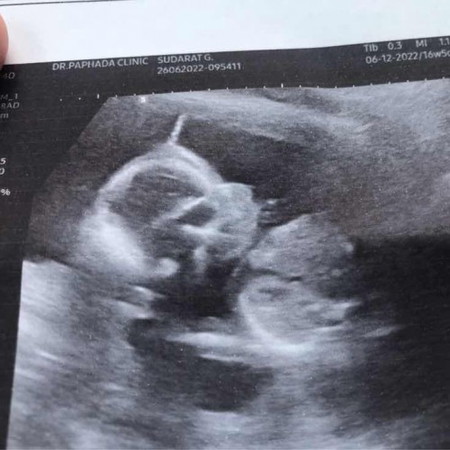

หนูน่ารักไหมค่ะ

คุณหมอบอกว่า น่าจะเป็นลูกสาว🥰